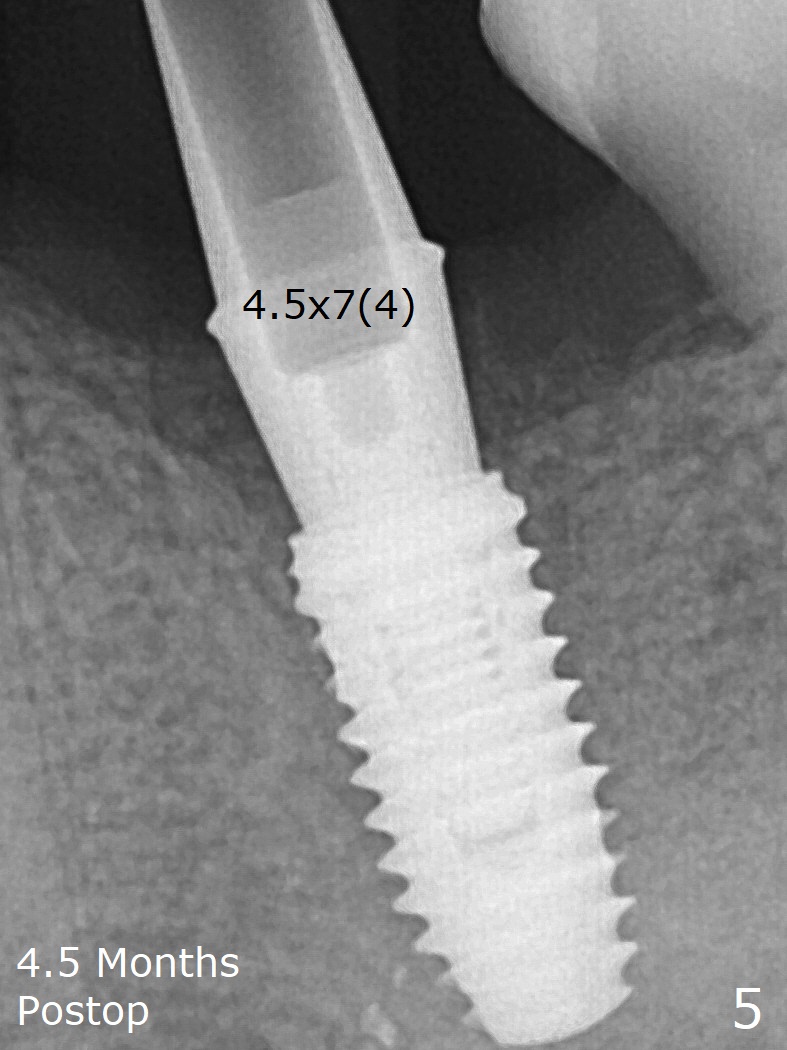

Since a 5.2x5.5(4) mm cemented abutment seems to be incompletely seated (Fig.4), a smaller one is placed with 30 Ncm without much improvement in seating (Fig.5). PAs are taken before and after cementation (Fig.6.7).